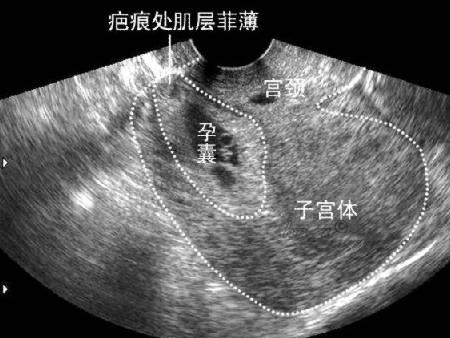

子宫瘢痕妊娠

子宫瘢痕妊娠图片

子宫瘢痕妊娠超声图片

瘢痕妊娠超声图片